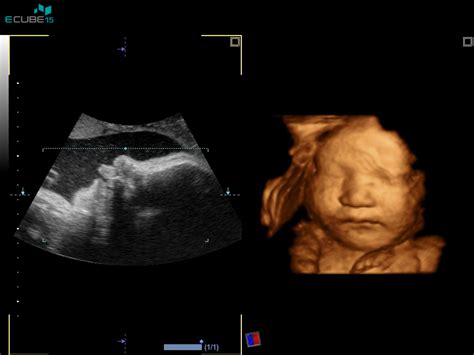

Razvoj lasnih mešičkov pri plodu se prične že zgodaj v nosečnosti. Ključno obdobje za razvoj las je med 14. in 15. tednom nosečnosti, ko se začnejo oblikovati prvi lasni mešički. Vendar pa vidni lasje, ki jih lahko opazimo na ultrazvoku ali celo otipamo po rojstvu, postanejo bolj izraziti v poznejših tednih nosečnosti. Nekateri viri navajajo, da lahko že okoli 16. tedna nosečnosti plod razvije tanke, svilnate dlačice, imenovane lanugo, ki prekrivajo večino njegovega telesa, vključno z glavo. Ti prvi lasje so pogosto zelo nežni in tanki.

Nekatere nosečnice poročajo, da so v obdobjih, ko so čutile močnejšo zgago, na ultrazvoku opazili, da ima njihov dojenček že kar lepo razvit »cupko«. Na primer, ena izmed mamic je omenila, da jo je med 31. in 33. tednom nosečnosti močno pekla kislina in se ji je spahovalo, dojenček pa je imel na UZ že lepe lase. V 34. tednu so težave popustile. Druga mamica pa je imela dve zelo »čupasti« hčerki, pa je kljub temu ni pekla zgaga. To kaže na individualne razlike in nezanesljivost te povezave.